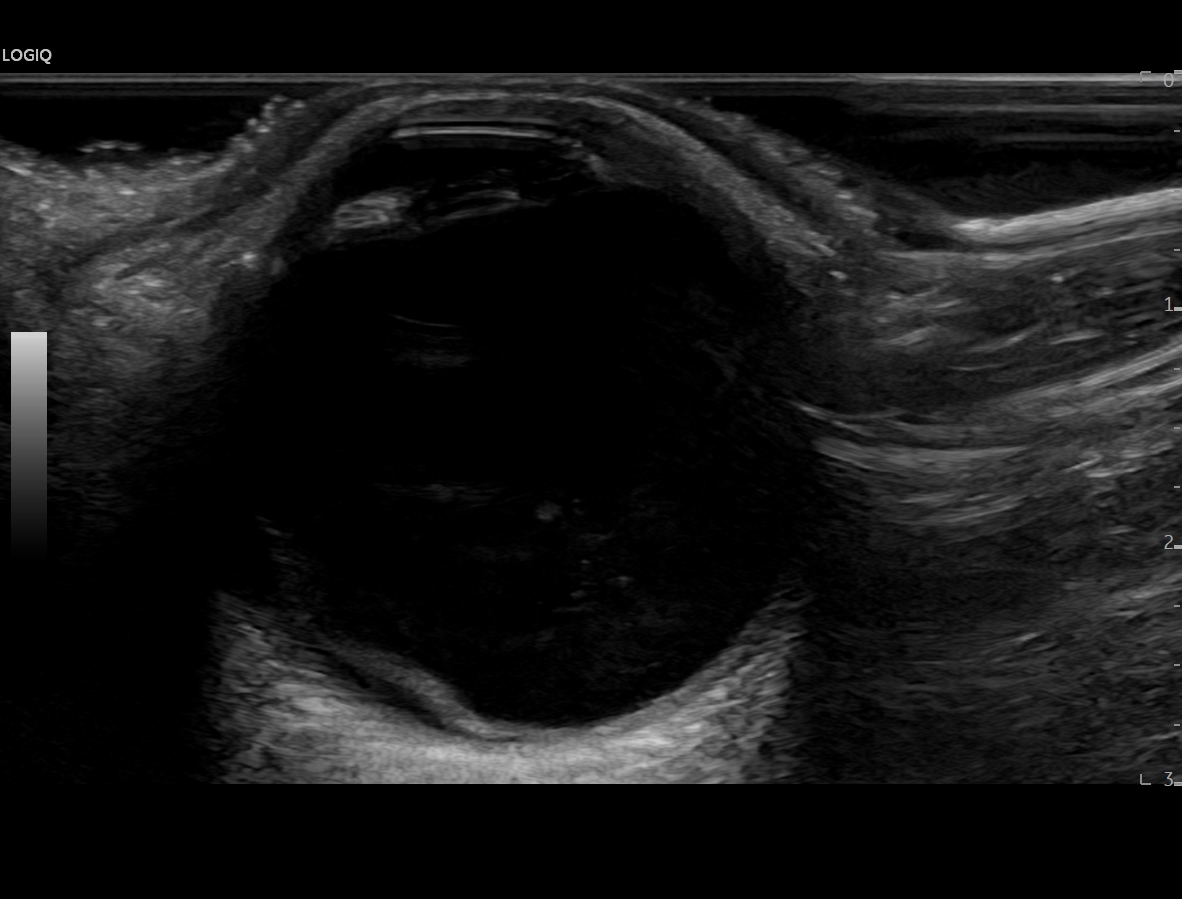

En urgencias hospitalarias se valora presión intraocular de ojo derecho en 12 mmHg y se realiza ecografía clínica del ojo con sonda plana, apreciando la imagen de sospecha de desprendimiento de vítreo posterior al apreciar una capa flotante en la porción posterior del mismo que en condiciones normales, no debería visualizarse.

Dado que la paciente no tiene antecedentes personales ni factores de riesgo cardiovascular, no parece corresponderse con una degeneración macular ni un desprendimiento de retina, aunque sí parece impresionar de un desprendimiento de vítreo posterior como posible causa inicial.